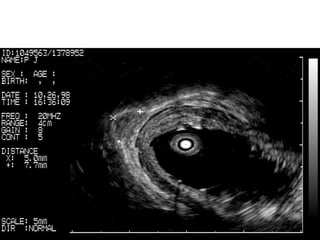

MALTOMA in stomach:

MALTOMA in stomach: MALT involving Muscularis